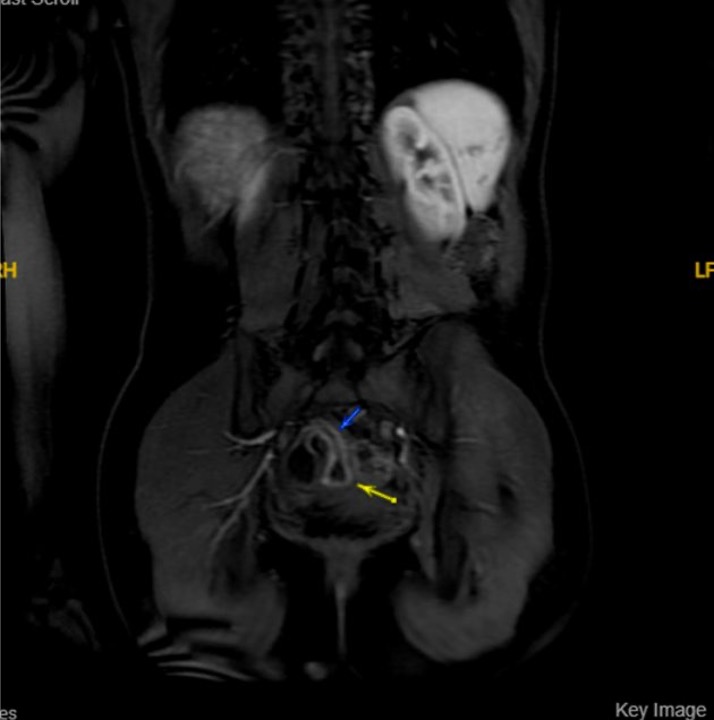

MRE:

- 8 cm of terminal ileal thickening consistent with a known diagnosis of Crohn’s disease. No abscess. No stricture noted.